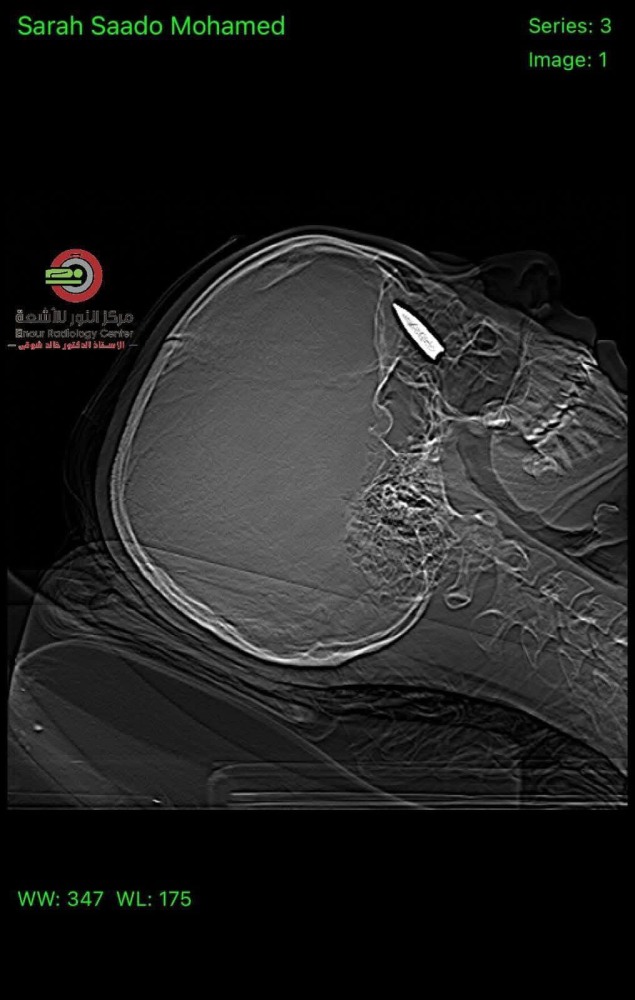

تمكن فريق طبي مصري من إزالة رصاصة من جمجمة فتاة فلسطينية من قطاع غزة نُقلت لتلقي العلاج في مصر.

وقالت بوابة الأهرام المصرية إن الفتاة كانت قد أصيبت بطلق ناري اخترق الجمجمة واستقر خلف العين، جراء إطلاق مسيَّرة إسرائيلية النار على نازحين في النصيرات وسط قطاع غزة. ووصفت الصحيفة الحكومية العملية بأنها كانت “أشبه بمعجزة”.

وقالت مؤسسة فجر الخيرية، التي كانت مسؤولة عن إجلاء سارة (18 عامًا)، إن الفتاة أصيبت بطلق في رأسها في أكتوبر، أدى إلى كسر في الجمجمة وإصابة في العصب البصري ونزيف في شبكة العين.